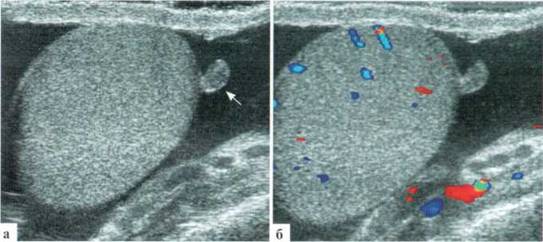

Рис. 1.1. Неизмененные яички у детей различных возрастных групп:

1 — яичко, 2 — придаток яичка, 3 — жидкостное содержимое в оболочках; а, б — В—режим и ДДС: яичко здорового новорожденного. В оболочках яичка содержится немного жидкости, интратестикулярный сосудистый рисунок прослеживается достоверно; а, г — ребенок 6 лет. Хорошо выражено средостение яичка (стрелка);

(), е — яичко подростка. Средостение вне скана